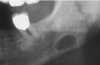

stafne defect